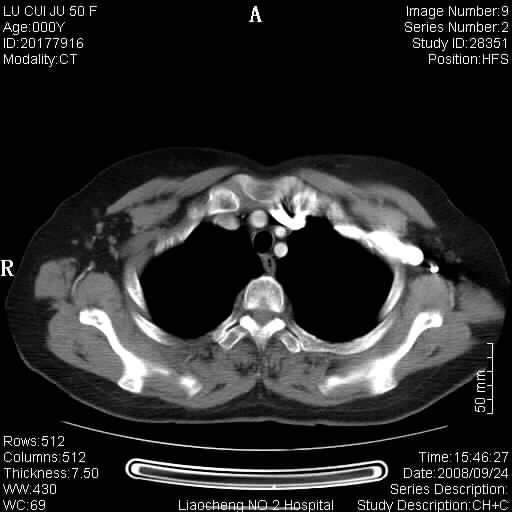

标题: CT15870:F50Y,纵膈占位,是不是胸腺瘤,请各位高手讨论。

临床表现为重症肌无力;ct增强扫描可见前纵膈胸腺部位弥漫性簇状软组织节结灶,不知道是不是胸腺瘤,请各位高手讨论。

胸腺外缘稍向外突,未见确切占位改变。结合临床考虑胸腺增生可能性大。

考虑胸腺增生!!

胸腺组织残留